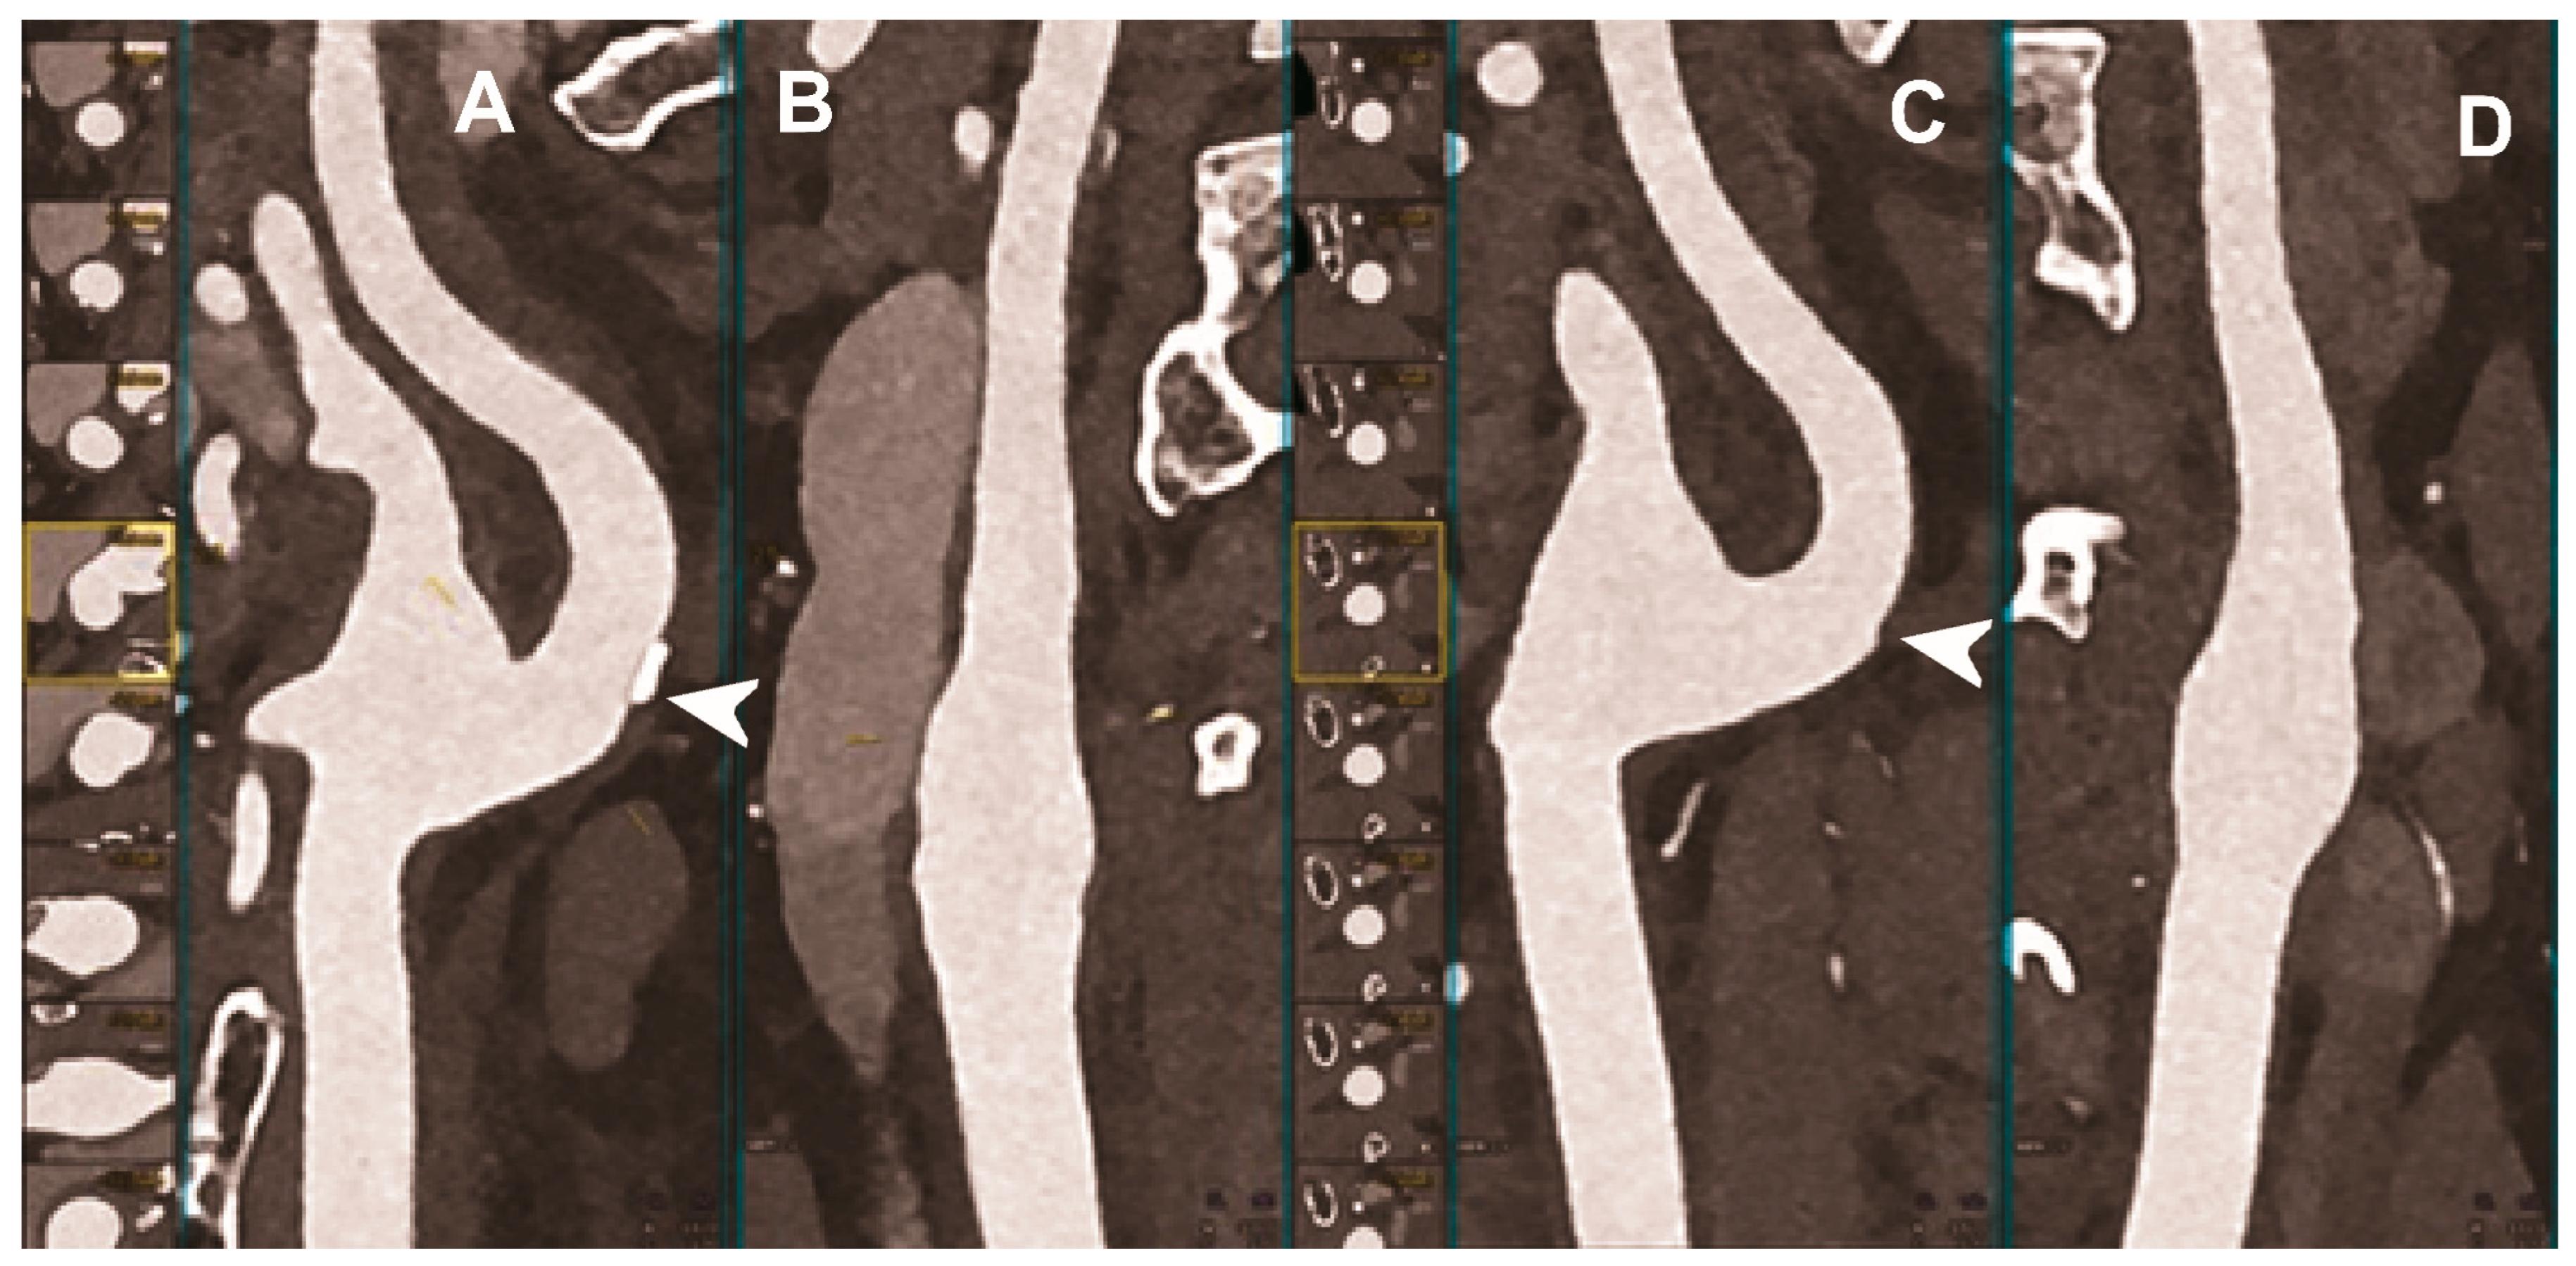

Figure 3.

Carotid CT angiography using photon-counting computed tomography. The figure shows advanced reconstructions of a carotid artery tree derived from a photon-counting CT (Scanner: NAEOTOM Alpha, Siemens) acquisition (A–D). In (A), a longitudinal multiplanar reconstruction shows the right common and internal carotid artery with no significant luminal stenosis and a predominantly calcified atherosclerotic plaque at the carotid bifurcation (arrowhead). In (B), a longitudinal multiplanar reconstruction shows the left common and internal carotid artery with a significant luminal stenosis in the post-bulbar region of the internal carotid artery (arrowhead). In (C) the quantitative assessment of the stenosis (arrowhead) and in (D) the 3-dimensional volume rendering of the lesion (arrowhead).

Figure 4.

Carotid CT angiography using photon-counting computed tomography. The figure shows advanced reconstructions of a carotid artery tree derived from a photon-counting CT (Scanner: NAEOTOM Alpha, Siemens) acquisition (A–D). In (A,B), a longitudinal multiplanar reconstruction shows the right common and internal carotid artery with no significant luminal stenosis and a mild predominantly calcified atherosclerotic plaque at the internal carotid origin (arrowhead). In (C,D), a longitudinal multiplanar reconstruction shows the left common and internal carotid artery with a minimal arterial wall irregularity at the internal carotid origin (arrowhead). What is a bit unusual is to be able to see the thickness of the arterial wall at this level in a case with very mild atherosclerotic disease.

The capability of PCCT technology to improve carotid and intracranial angiography has been demonstrated in vivo in a pilot study involving 16 asymptomatic subjects [49]. Compared to conventional CT, PCCT offered less image noise (9%) and beam-hardening artifacts in internal carotids close to the surrounding bone. Accordingly, the two radiologists blinded to the detector subsystem attributed to the images obtained with PCCT significantly higher quality scores for all vascular segments. Finally, the above-mentioned study showed the feasibility of spectral material decomposition of PCCT in the neck and brain for vascular imaging, although a direct comparison of the spectral performance between PCD and comparable dual energy EID CT scanners was not performed.